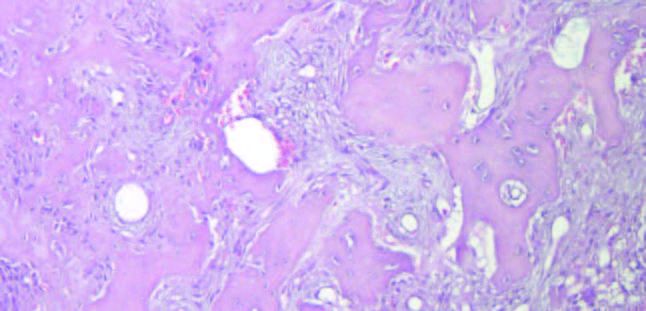

El análisis mediante tinciones de Hematoxilina-Eosina y Tricrómico de Masson, mostró una lesión fibro-ósea constituida por tejido conectivo fibroso con abundante celularidad fusiforme que rodeaba fragmentos trabeculares de tejido cemento-óseo vital con aposición celular blástica externa y clástica multinuclear, lo que confirma el diagnóstico de DCOF (Figuras 6 y 7).

Histológicamente, todas las variantes de DCO tienen características microscópicas similares; un tejido mesenquimatoso de celularidad variable, compuesto por fibroblastos fusiformes, fibras colágenas y vasos sanguíneos, entremezclado con tejido mineralizado que consiste en osteoide, hueso reticulado y material similar al cemento, que se disponen en forma de trabéculas y osículos/cementículos irregulares y coalescentes. Durante la maduración, la matriz se fusiona para formar depósitos más grandes e hipocelulares con líneas de cemento irregulares. Es común encontrar hemorragia, especialmente cerca de la periferia, lo cual puede atribuirse a la fragilidad vascular en el tejido conectivo alterado presente en la DCO3,13.